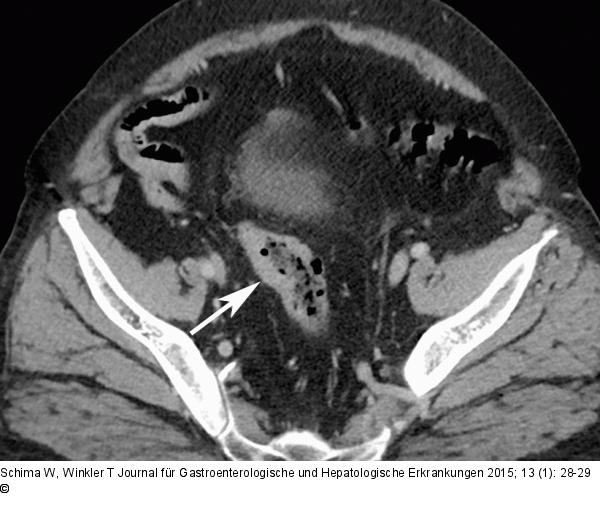

Abbildung 1a: Intrapankreatische Nebenmilz Die axiale KM-verstärkte MDCT zum Staging zeigt eine Wandverdickung des C. sigmoideum, dem bekannten Adenokarzinom entsprechend (Pfeil). |

Die axiale KM-verstärkte MDCT zum Staging zeigt eine Wandverdickung des C. sigmoideum, dem bekannten Adenokarzinom entsprechend (Pfeil). |